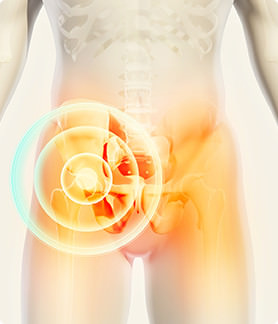

全人工股関節置換術(Total Hip Arthroplasty:THA)|関節とは | 人工関節と関節痛の情報サイト 【関節が痛い.com】

全人工股関節置換術(Total Hip Arthroplasty:THA)|関節とは | 人工関節と関節痛の情報サイト 【関節が痛い.com】

全人工股関節置換術(Total Hip Arthroplasty:THA)|関節とは | 人工関節と関節痛の情報サイト 【関節が痛い.com】,

全人工股関節置換術(Total Hip Arthroplasty:THA)|関節とは | 人工関節と関節痛の情報サイト 【関節が痛い.com】, 変形性股関節症、人工股関節全置換術について塗山先生が徹底解説,

変形性股関節症、人工股関節全置換術について塗山先生が徹底解説,-300x173.jpg) 変形性股関節症(股関節痛でお悩みの方へ)【人工関節外科】 | おおさかグローバル整形外科病院 | 大阪市城東区 | 脊椎、人工関節、スポーツ整形、ペインクリニック | 牧ヘルスケアグループ | 医療法人 清翠会,

変形性股関節症(股関節痛でお悩みの方へ)【人工関節外科】 | おおさかグローバル整形外科病院 | 大阪市城東区 | 脊椎、人工関節、スポーツ整形、ペインクリニック | 牧ヘルスケアグループ | 医療法人 清翠会,-300x206.jpg) 変形性股関節症(股関節痛でお悩みの方へ)【人工関節外科】 | おおさかグローバル整形外科病院 | 大阪市城東区 | 脊椎、人工関節、スポーツ整形、ペインクリニック | 牧ヘルスケアグループ | 医療法人 清翠会,

変形性股関節症(股関節痛でお悩みの方へ)【人工関節外科】 | おおさかグローバル整形外科病院 | 大阪市城東区 | 脊椎、人工関節、スポーツ整形、ペインクリニック | 牧ヘルスケアグループ | 医療法人 清翠会, 変形性股関節症、人工股関節全置換術について塗山先生が徹底解説

変形性股関節症、人工股関節全置換術について塗山先生が徹底解説